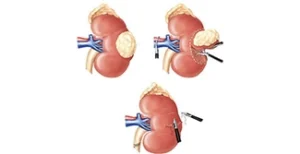

A nefrectomia parcial robótica é uma cirurgia minimamente invasiva para remover tumores renais, preservando o órgão. O cirurgião usa um console 3D para controlar braços robóticos inseridos por pequenas incisões.

Cirurgia para retirada parcial ou total do rim afetado por tumor, realizada com alta precisão robótica e foco em preservar o máximo possível da função renal.